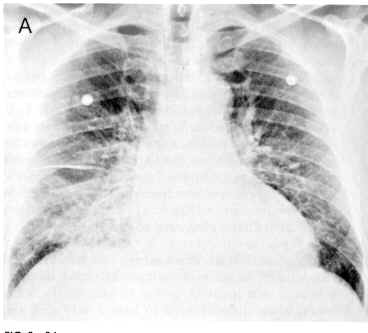

Pulmonary edema is common in congestive heart failure.

As pulmonary capillary pressures increase, the initial fluid excess is removed by increased lymphatic drainage.

When lymphatic system capacity is exceeded, pulmonary edema occurs.

Radiographic signs include septal lines, bronchial wall thickening and subpleural pulmonary edema.

This radiograph illustrates generalized fissural thickening and lack of clarity of intrapulmonary vessels and septal lines.

Figure above and description from "Imaging Diseases of the Chest" , p. 388, by Peter Armstrong, Alan G. Wilson, and Paul Dee, Yearbook Medical Publishers, Inc. 1990.